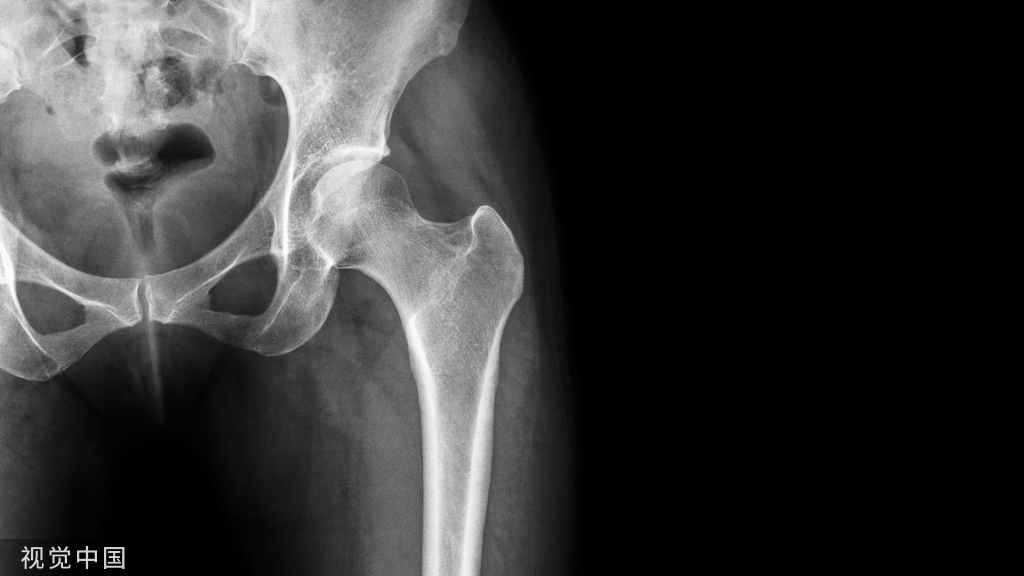

为了更好地理解普通型DTFH的损伤机制,以1例患者的图像资料为例加以解读。X线前后位和侧位见右侧髋关节脱位、合并同侧股骨头骨折和股骨颈骨折。股骨头离开髋臼位于髋臼下方,可见一大一小2个部分重叠的股骨头骨折影,髋臼呈空虚状态(图1a-1b)。CT三维重建见股骨颈骨折为头下型骨折,骨折完全移位。

(图左)骨盆前后位 X 线片

(图右)髋关节侧位 X 线片